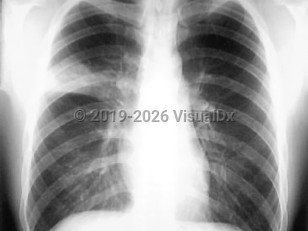

InfluenzaInfluenza